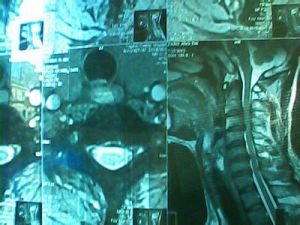

MRI檢查

MRI檢查對頸椎間盤突出症的診斷具有重要價值。其準確率明顯高於CT檢查和脊髓造影。在MRI片上可直接觀察到椎間盤向後突入椎管內,椎間盤突出成分與殘餘髓核的信號強度基本一致。在中央型頸椎間盤突出者,可見突出椎間盤明顯壓迫頸髓,使之局部變扁或出現凹陷,受壓部位的頸髓信號異常。在側方型頸椎間盤突出者,可見突出的椎間盤使頸髓側方受壓變形,信號強度改變,神經根部消失或向後移位。